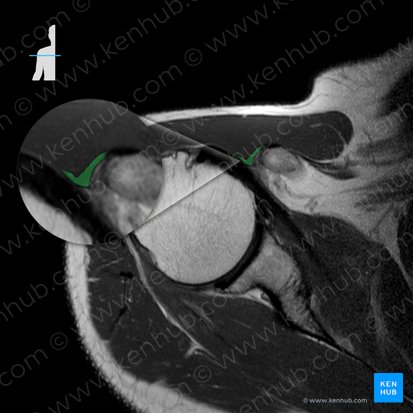

Das Labrum glenoideum lässt sich am deutlichsten in der axialen Schnittebene beurteilen. Es erscheint auf der vorderen und hinteren Kante der Fossa glenoidea als zwei dreieckige, hypointense Strukturen. Während der Beurteilung des Labrum glenoideum sollte man auf Risse oder Ablösungen achten. Diese krankhaften Veränderungen würden als Flüssigkeit zwischen dem Labrum und der knöchernen Fossa glenoidea oder als Labrum-Abbruch auf dem MRT erscheinen.